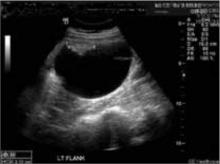

FIGURE 2 US scan at 18 weeks

Teratoma or solid component of the collision tumor.At 7 weeks’ gestation, I performed her first pelvic exam, during which I palpated a mass in the left adnexa. The patient was asymptomatic. US imaging revealed a complex cystic mass measuring 4.7 × 4.4 × 3.7 cm on the left ovary and a viable 9-week gestation in the uterus (FIGURE 1). A repeat US at 18 weeks revealed that the mass had increased in size to 7.5 × 6.9 × 3.7 cm (FIGURE 2). The patient (and her mother) refused resection, so a follow-up scan was scheduled. The patient remained asymptomatic.

Serous cystadenoma or cystic component of the collision tumor.Follow-up scans were performed over the remainder of the pregnancy, and the mass eventually reached 13.3 cm at its greatest dimension. At 28 weeks, the family again refused resection, opting to wait until term. The patient was placed on bed rest. Primary cesarean delivery was performed at term because the fetus was unengaged. The mass was resected without any complications to infant or mother (FIGURE 3). The infant was a viable male with Apgar scores of 8 and 9, and mother and baby were discharged after 72 hours.